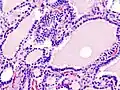

Hyperthyroidism is one of the most common endocrine conditions affecting older domesticated housecats. In the United States, up to 10% of cats over ten years old have hyperthyroidism.[64] The disease has become significantly more common since the first reports of feline hyperthyroidism in the 1970s. The most common cause of hyperthyroidism in cats is the presence of benign tumors called adenomas. 98% of cases are caused by the presence of an adenoma,[65] but the reason these cats develop such tumors continues to be studied.

The most common presenting symptoms are: rapid weight loss, tachycardia (rapid heart rate), vomiting, diarrhea, increased consumption of fluids (polydipsia), increased appetite (polyphagia), and increased urine production (polyuria). Other symptoms include hyperactivity, possible aggression, an unkempt appearance, and large, thick claws. Heart murmurs and a gallop rhythm can develop due to secondary hypertrophic cardiomyopathy. About 70% of affected cats also have enlarged thyroid glands (goiter). 10% of cats exhibit "apathetic hyperthyroidism", which is characterized by anorexia and lethargy.[66]